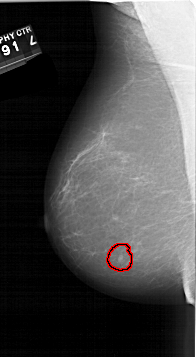

A_1541_1.LEFT_CC

LEFT_CC LINES 6676 PIXELS_PER_LINE 3376 BITS_PER_PIXEL 12 RESOLUTION 43.5 OVERLAY

FILE: A_1541_1.LEFT_CC.OVERLAY

TOTAL_ABNORMALITIES 1

ABNORMALITY 1

LESION_TYPE MASS SHAPE OVAL MARGINS CIRCUMSCRIBED

ASSESSMENT 4

SUBTLETY 4

PATHOLOGY BENIGN

TOTAL_OUTLINES 1

BOUNDARY